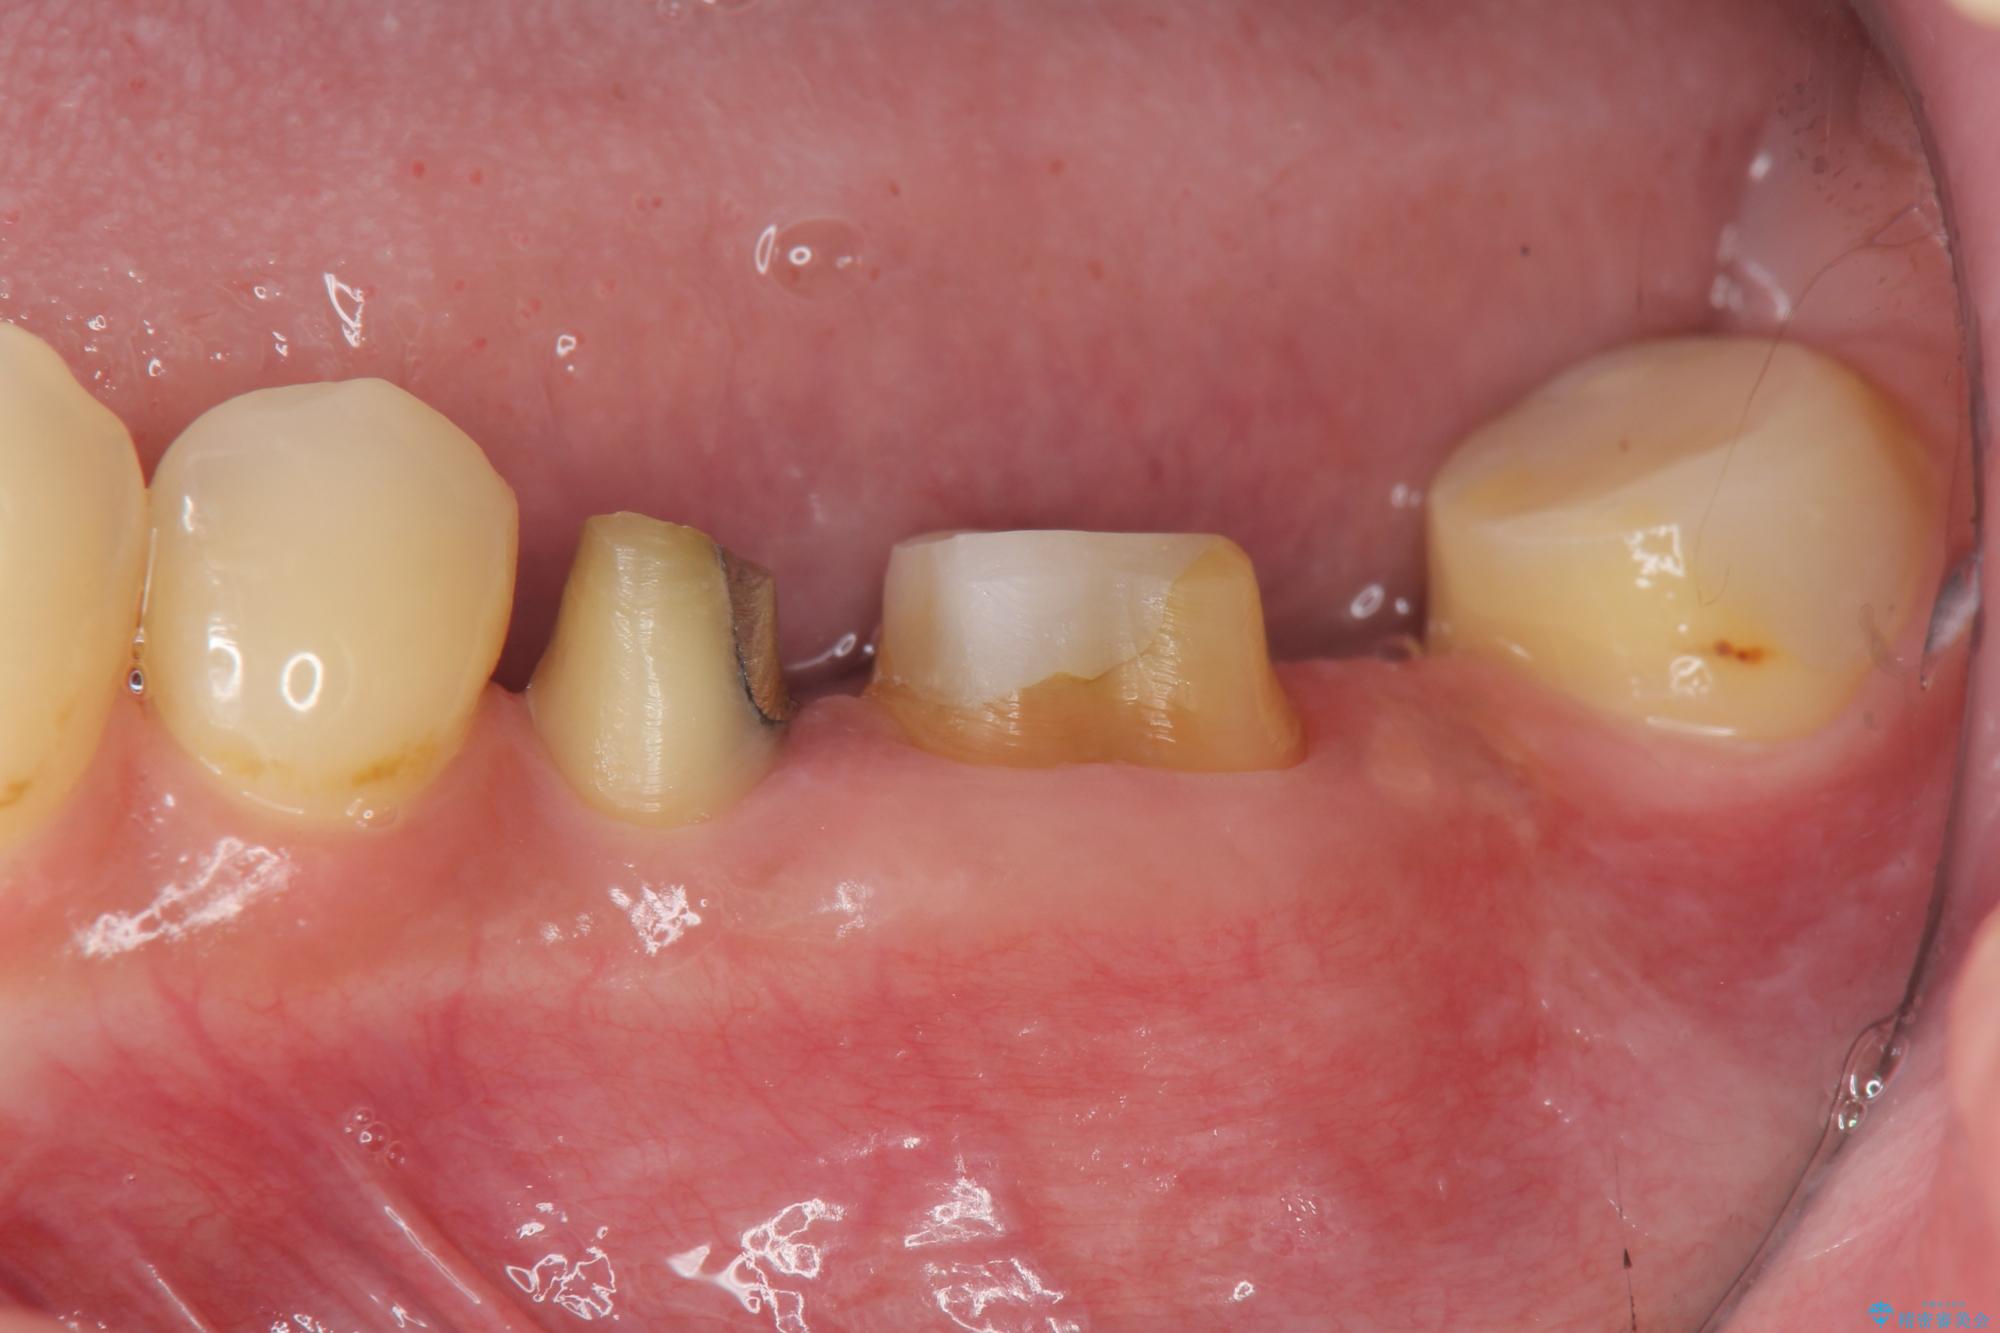

- 他院で根の治療まで終え、違和感が取れず相談に来院されました。

当該歯を精査したところ、歯根に破折が見られ抜歯を余儀なくされました。